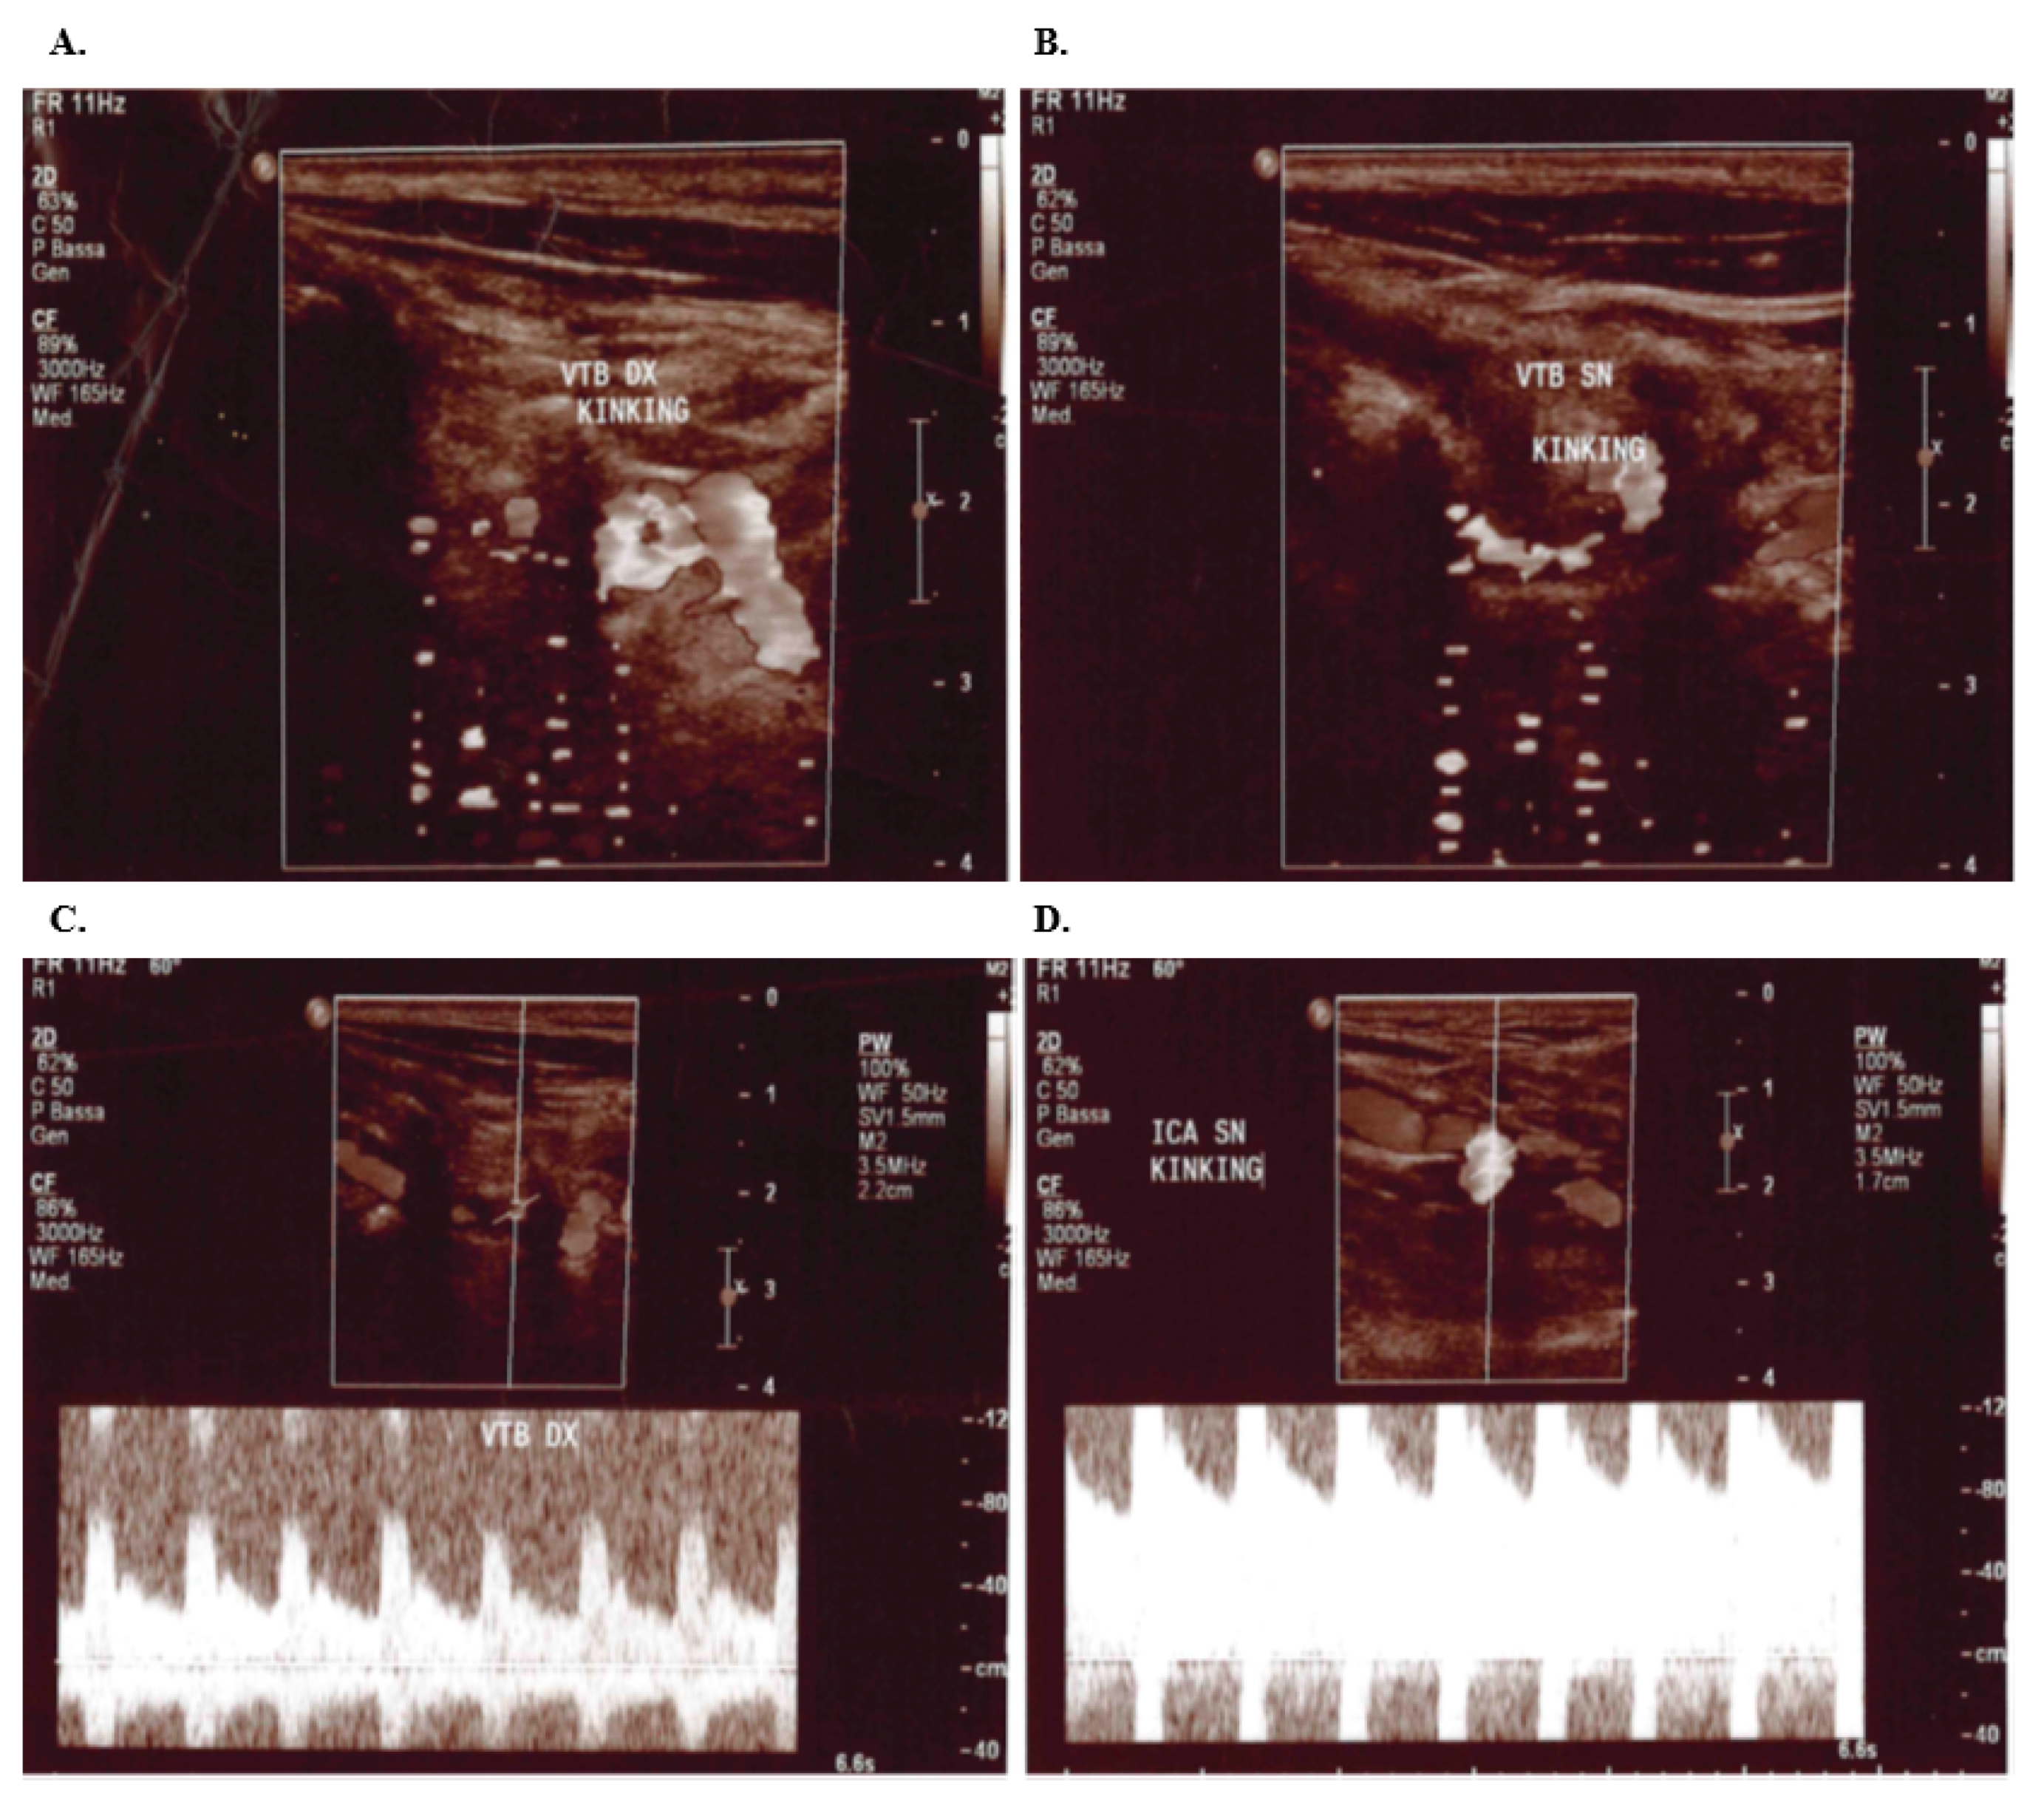

2. Case Presentation